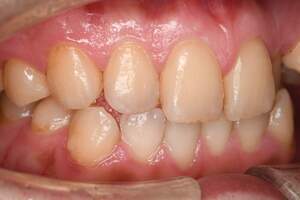

歯石除去

治療前

治療後

| 年齢 | 31歳・女性 |

| 主訴 | 主訴:歯石除去 部位:全顎 |

| 治療内容 | 初診検査・歯石除去 |

| 治療期間 | 2週間 |

| 費用 | 合計:約4,000~5,000円 内訳 初診料:約3,000~4,000円 (保険診療) 歯石除去:約1,000円 (2023年1月現在) |

| リスク・副作用 | ・歯肉の炎症がある場合は歯石除去中に出血を伴う可能性があります。 ・処置後に歯がしみることがあります。 ・歯茎の炎症が軽減すると歯茎が引き締まり、歯が長く見えることがあります。 |

| 治療方針 | 前歯部に叢生(歯列不正)があり多量の歯石が認められました。炎症の抑制を優先するため初診時はTBIのみ行い、2回目以降で歯石除去を行いました。今後は縁下歯石(歯ぐきの中に付着する歯石)の除去を全顎的に行っていく予定です。 |

| 担当者所見 | 叢生(そうせい)とは歯が折り重なるようにデコボコにはえている状態をいいます。歯ブラシが難しく磨き残しをしやすい為、普段使用している歯ブラシに加えワンタフトという細かい部分も磨くことのできる小さな毛束の歯ブラシの使用をおすすめしました。 |

| 担当者所見 | 歯石の存在は感じていたものの歯科医院に苦手意識が強く3年ほど放置していたとのことでした。 舌で触った時にザラザラすることや口臭も気になった為、今回意を決してご来院くださいました。 ブラッシング指導を熱心に聞いてくださり、セルフケアで歯肉の炎症を抑えた上で歯石除去ができたのでお痛みが少なく行えました。 患者様も苦手意識が克服できたと喜んでくださり、今後の治療にも積極的な姿勢です。 |